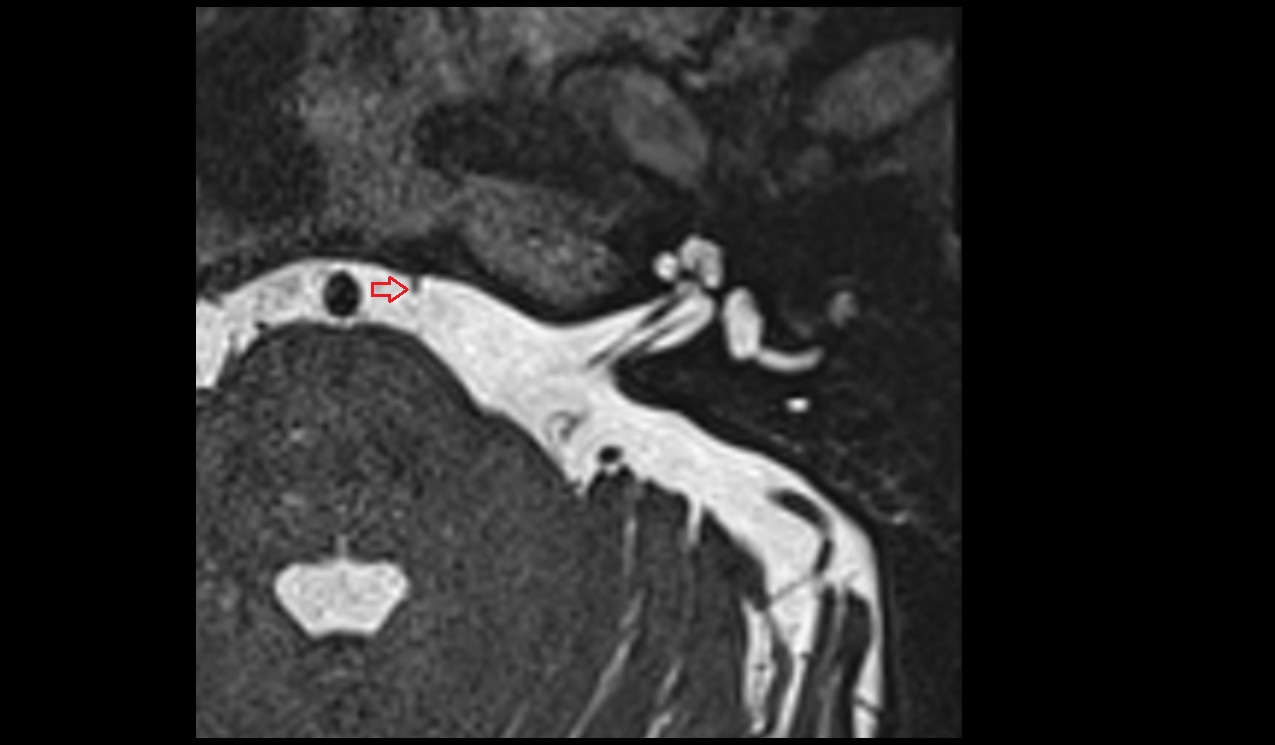

- Mandibular canal

- Inferior alveolar nerve

- inferior alveolar artery

- Mandibular foramen